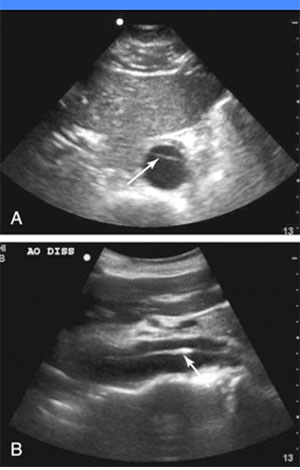

این هم یک کیس دایسکشن آئورت شکمی هست که فلپ با فلش نشون داده شده :